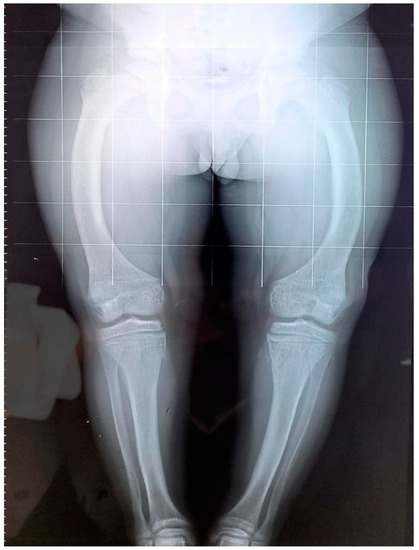

3.1. Patient 1

3.2. Patient 2